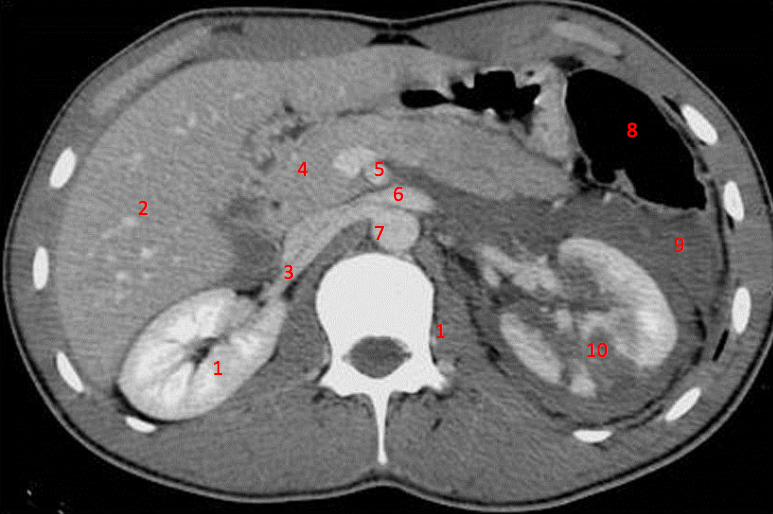

1

Number 3?

IVC

2

Number 1?

R Kidney

3

5

4

A

How well did you know this?

Not at all